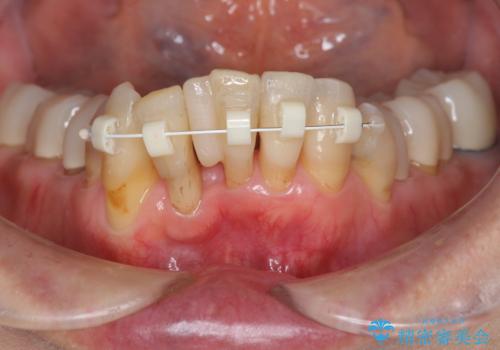

- 上顎前歯の黒ずみの改善、下顎前歯の十度なガタつき、矯正治療とセラミック治療を含む全体的な治療を希望され来院されました。

銀歯を高強度の仮歯に替えたのち、下顎前歯のみの部分矯正→全体的なマウスピース矯正治療(インビザライン)→最終的なセラミック治療と治療を進めます。

矯正治療と目立つ銀歯のやりかえを行ったことでかみあわせだけでなく、審美性・清掃性も改善し口腔内の環境を劇的に改善することができました。